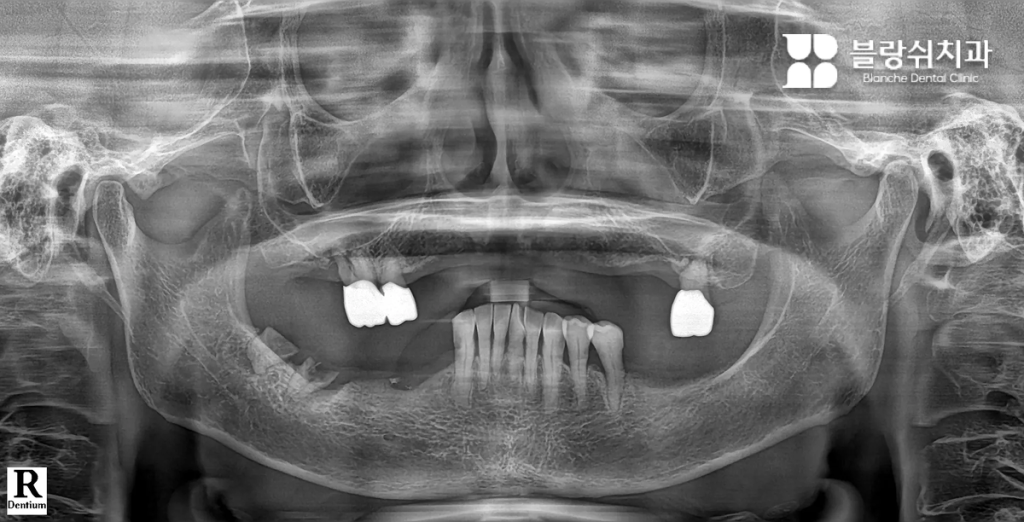

디지털 풀아치 임플란트는 한 턱에 4~6개의 임플란트로 전체 치아 기능을 회복하는 치료입니다. 먼저 3D CT, 파노라마, 디지털 구강 스캐너를 통해 잇몸뼈의 두께·밀도·신경 위치를 3차원으로 분석합니다. 이 단계에서 임플란트가 가능한 뼈 영역과 피해야 할 위험 구간을 명확히 구분합니다.

- 치료 후 변화 “이제는 음식 종류를 가리지 않고 먹을 수 있어서 삶의 만족도가 확실히 달라졌습니다.” 디지털 스캔 데이터를 기반으로 3D 치료 계획을 수립한 뒤, 컴퓨터 가이드 수술로 임플란트를 정확한 위치에 식립했습니다. 이후 CAD/CAM 기술로 제작된 풀아치 보철물을 장착하며 치료가 진행되었고, 적은 방문 횟수로 치료를 마칠 수 있었습니다.

- 디지털 풀아치 임플란트를 선택한 이유 상담 과정에서 디지털 풀아치 임플란트는 상대적으로 단단한 뼈 부위를 활용해 식립하기 때문에, 광범위한 뼈이식 없이도 치료할 수 있다는 설명을 들었습니다. 디지털 스캐닝과 시뮬레이션을 통해 환자분의 구강 상태에 맞춘 맞춤형 치료 계획이 세워졌고, 이를 바탕으로 치료를 결심하게 되었습니다.

- 치료 후 변화 “치아 때문에 받던 스트레스가 사라졌고, 일상생활로 빠르게 돌아갈 수 있었습니다.” 디지털 가이드를 활용한 수술로 치료가 진행되었고, 생각보다 짧은 기간 안에 치료가 마무리되었습니다. 환자분은 빠른 회복 속도에 만족감을 보였으며,

이 환자분은 20여 년간 틀니를 사용하셨습니다. 임플란트 시술 후 얼굴이 변하지 않을까 많은 고민을 하셨는데요. 특히 틀니를 제거하면 입이 안으로 들어가 보일까 걱정하셨습니다. 하지만 절대 그럴 일이 없다고 안심시켜드리며 디지털 풀아치 임플란트를 설명드렸습니다. 이 방법은 잇몸의 부피감까지 회복해 입술과 인중의 주름까지 개선할 수 있기 때문입니다.

위 사진처럼 그동안 틀니를 썼다는 것을 믿을 수 없을 정도로 얼굴이 좋아지셨습니다. 실제로 수술 이후 “주변에서 10년은 더 젊어 보인다고 해요”라는 말씀을 전해주셨습니다. 충분히 그럴 만합니다.